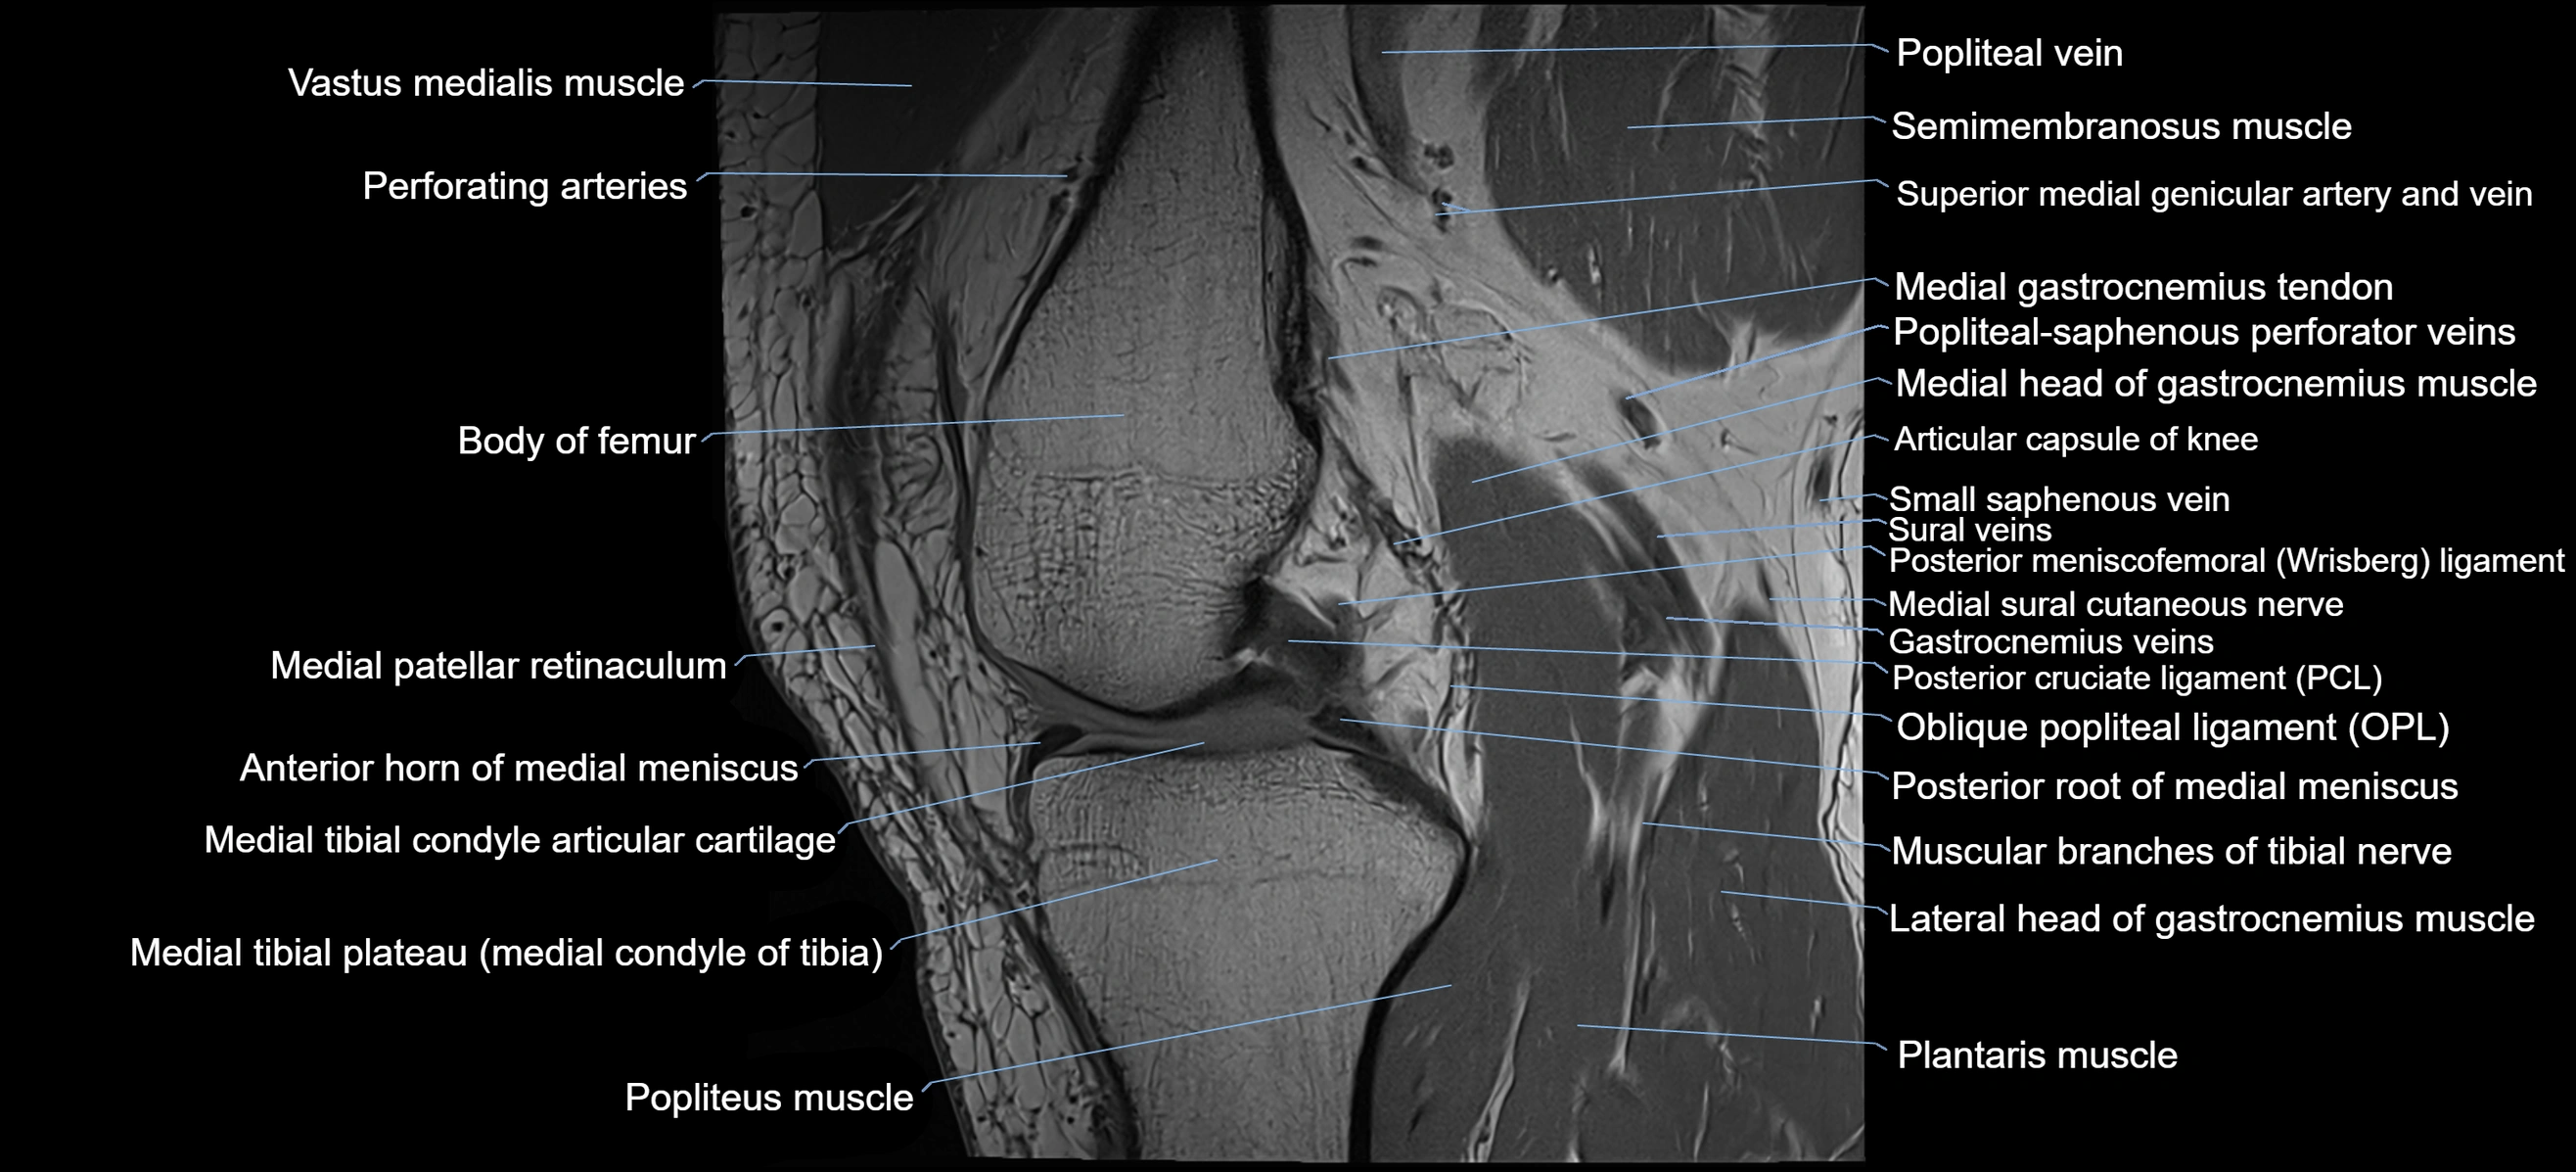

- Anterior horn of medial meniscus

- Body of femur

- Lateral head of gastrocnemius muscle

- Medial gastrocnemius tendon

- Medial head of gastrocnemius muscle

- Medial patellar retinaculum

- Medial sural cutaneous nerve

- Medial tibial plateau

- Muscular branches of tibial nerve

- Oblique popliteal ligament

- Plantaris muscle

- Popliteal vein

- Popliteal–Saphenous perforating veins

- Popliteus muscle

- Posterior cruciate ligament

- Posterior meniscofemoral ligament

- Posterior root of medial meniscus

- Small saphenous vein